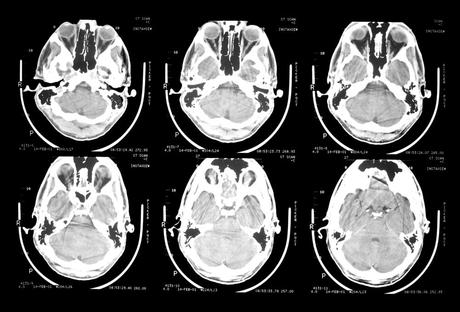

Las consecuencias del daño cerebral adquirido incluyen alteraciones en el funcionamiento cognitivo, emocional y conductual de las personas afectadas. La neuropsicología proporciona técnicas que permiten tratar dichas alteraciones; de ahí la importancia de establecer cuáles, de entre todas las herramientas disponibles, son las más eficaces para este objetivo.

El presente artículo revisa los estudios existentes sobre efectividad de la rehabilitación neuropsicológica, centrándose en aquellas áreas y procesos cognitivos alterados con más frecuencia. El fin último del artículo es servir de guía y orientar la rehabilitación neuropsicológica de estos pacientes a partir de las evidencias más sólidas existentes en la bibliografía. En esta segunda parte, nos centraremos en la rehabilitación de las funciones ejecutivas, la modificación de conducta y la psicoterapia aplicadas en este ámbito, así como el uso de nuevas tecnologías.